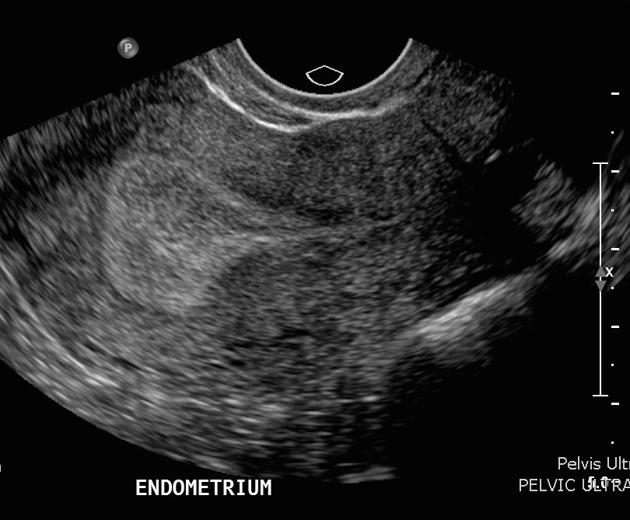

What endometrial phase do we see in this image?

Secretory